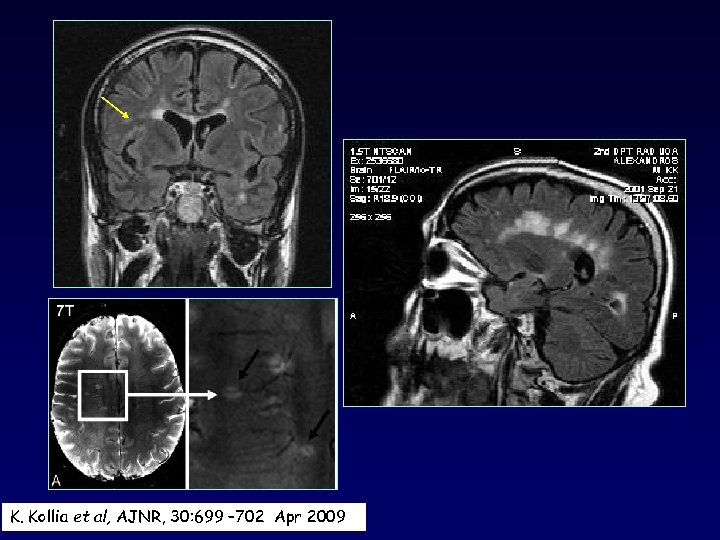

K. Kollia et al, AJNR, 30: 699 – 702 Apr 2009

Plaques along calososeptal interface and periventricular extension (Dawson fingers) (sensitivity 93%, specificity 98%) MA Gean et al. Radiology 1991 180: 215 -221